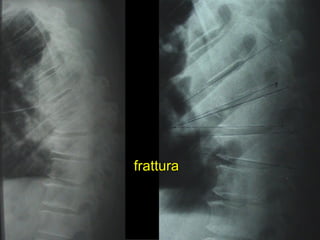

Tc pre op

frattura

TC RMN

Rx post